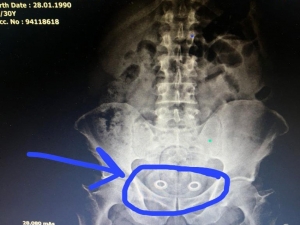

İran Uyruklu Bir Kişinin Mide Ve Bağırsağından Uyuşturucu Çıktı